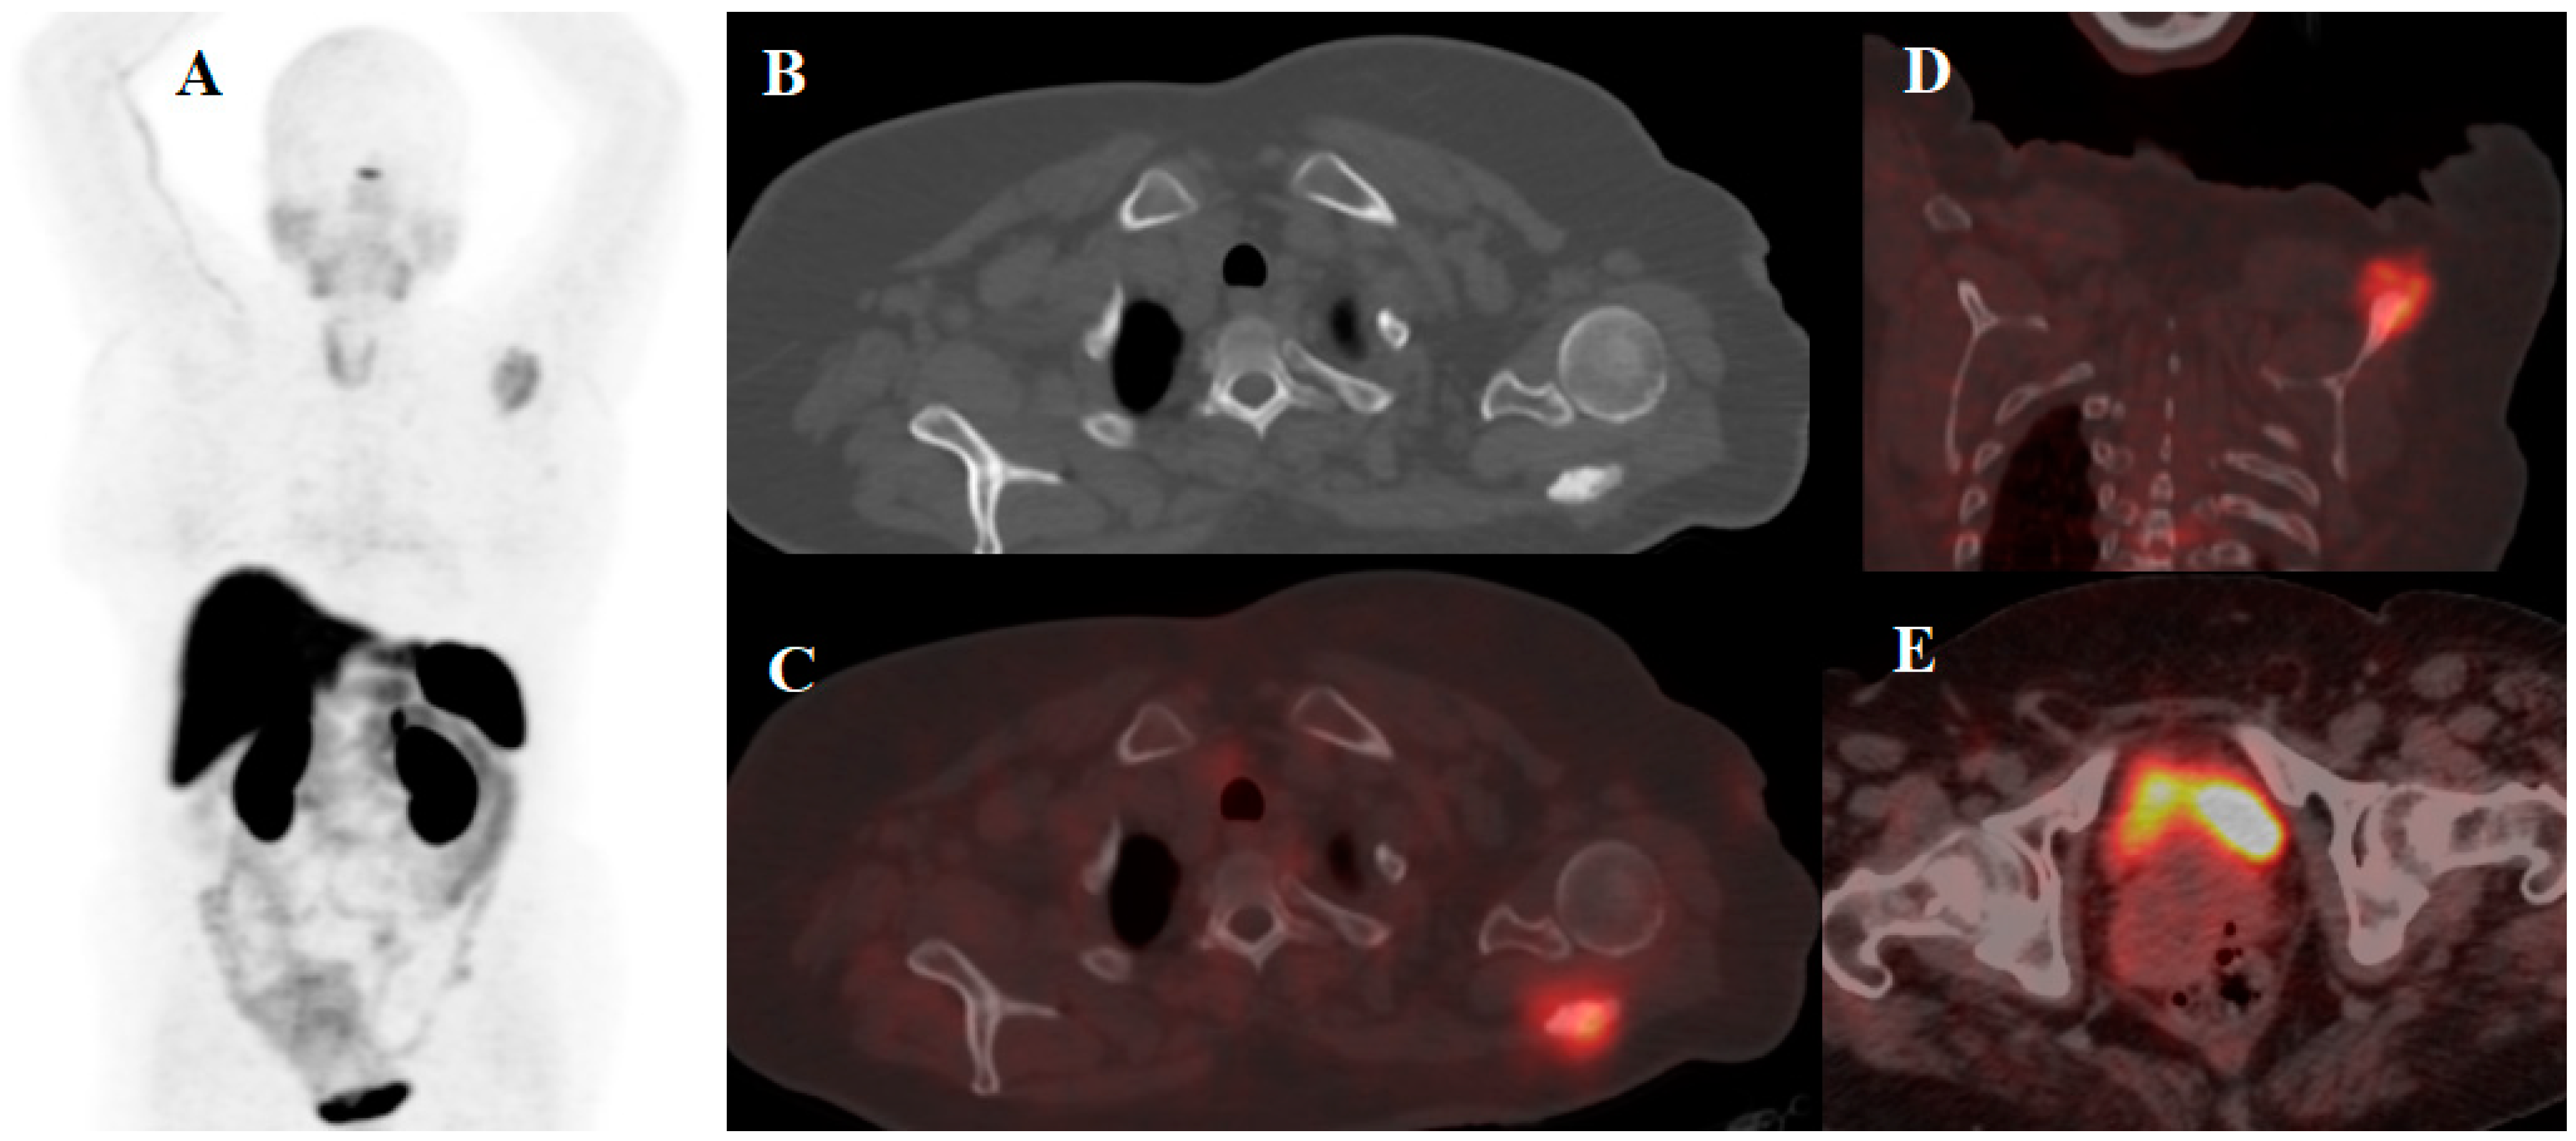

- Pfeifer, A.; Knigge, U.; Mortensen, J.; Oturai, P.; Berthelsen, A.K.; Loft, A.; Binderup, T.; Rasmussen, P.; Elema, D.; Klausen, T.L. Clinical PET of neuroendocrine tumors using 64Cu-DOTATATE: First-in-humans study. J. Nucl. Med. 2012, 53, 1207–1215. [Google Scholar] [CrossRef] [Green Version]

- Delpassand, E.S.; Ranganathan, D.; Wagh, N.; Shafie, A.; Gaber, A.; Abbasi, A.; Kjaer, A.; Tworowska, I.; Núñez, R. 64Cu-DOTATATE PET/CT for imaging patients with known or suspected somatostatin receptor–positive neuroendocrine tumors: Results of the first US prospective, reader-masked clinical trial. J. Nucl. Med. 2020, 61, 890–896. [Google Scholar] [CrossRef]

- Loft, M.; Carlsen, E.A.; Johnbeck, C.B.; Johannesen, H.H.; Binderup, T.; Pfeifer, A.; Mortensen, J.; Oturai, P.; Loft, A.; Berthelsen, A.K. 64Cu-DOTATATE PET in patients with neuroendocrine neoplasms: Prospective, head-to-head comparison of imaging at 1 hour and 3 hours after injection. J. Nucl. Med. 2021, 62, 73–80. [Google Scholar] [CrossRef] [PubMed]

| [64Cu]Cu-DOTA-Octreotide Derivatives | Disease | Patients Included in the Study | Year | Result | Refs. |

|---|---|---|---|---|---|

| [64Cu]Cu-DOTA-TATE | NET | 12 patients divided into 3 dose groups | 2020 | This protocol was introduced as a safe imaging method provides high quality and accurate images using optimal dose of 148 MBq (4.0 mCi) injection | [92] |

| NET | 60 | 2015 | Potential role of 64Cu-DOTATATE in the assessment of atherosclerosis was confirmed | [23] | |

| NEN | 128 | 2020 | The study demonstrated prediction potency of [64Cu]Cu-DOTA-TATE in PFS | [24] | |

| NET | 112 | 2015 | Superiority of [64Cu]Cu-DOTA-TATE over [111In]In-DTPA-OC was proved | [5] | |

| NEN | 35 | 2020 | Excellent performance of [64Cu]Cu-DOTA-TATE PET/CT during 1–3 h after injection was clarified | [95] | |

| [64Cu]Cu-DOTA-TOC | NET | 33 | 2019 | High detection rate and high target to background ratio in images raised [64Cu]Cu- DOTA-TATE as a promising and safe radiolabeled SST derivative for NET detection | [22] |